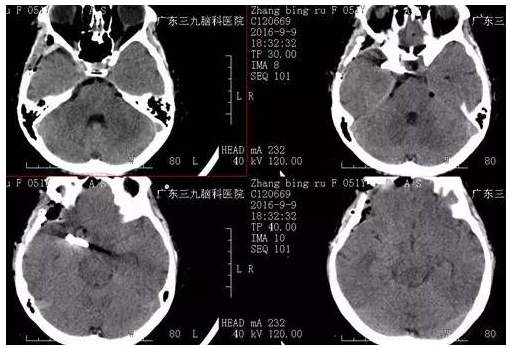

术后▲

手术由神经外一科主任张良博士主刀完成,完善术前检查后,在全麻下行“右侧后交通动脉瘤夹闭术”,经系统治疗后患者颞部疼痛及眼睑下垂症状较前缓解康复出院。